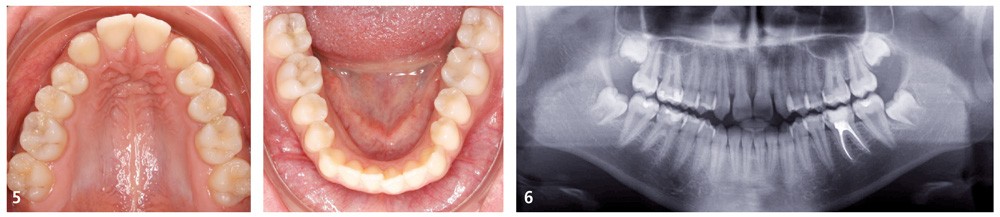

La jeune patiente présente, à l’examen clinique extra-oral, une tendance classe III qui se traduit par une protrusion de la lèvre inférieure de profil, et un menton très présent lors du sourire (fig. 1). À l’examen intra-oral, l’arcade maxillaire est en V, les incisives latérales permanentes droite (12) et gauche (22) sont manquantes et les espaces presque refermés. À l’arcade mandibulaire, un léger encombrement incisif est présent. En occlusion, elle présente une classe I molaire et canine et une occlusion inversée antérieure qui se prolonge à droite sur la première prémolaire (14) (fig. 2 à 5).

La radiographie panoramique (fig. 6) confirme le diagnostic d’agénésies des incisives latérales maxillaires et indique la présence de lésions carieuses proximales sur les molaires mandibulaires, à soigner avant de débuter le traitement.

L’examen de la téléradiographie de profil révèle une classe I squelettique (ANB = 1°) dans un contexte normodivergent (FMA = 23°). On note l’incisive maxillaire à 103° et l’incisive mandibulaire à 97° (fig. 7).